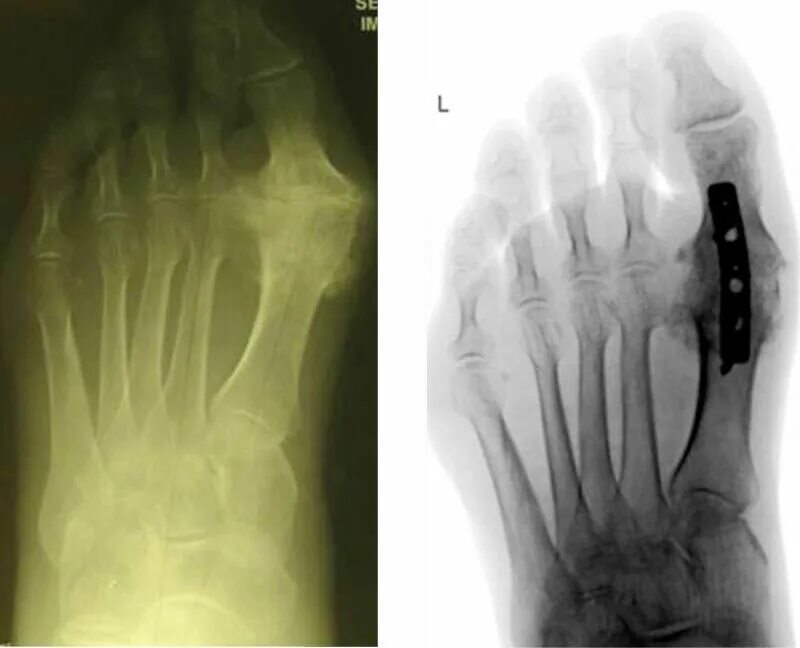

Артроз плюснефалангового сустава стопы